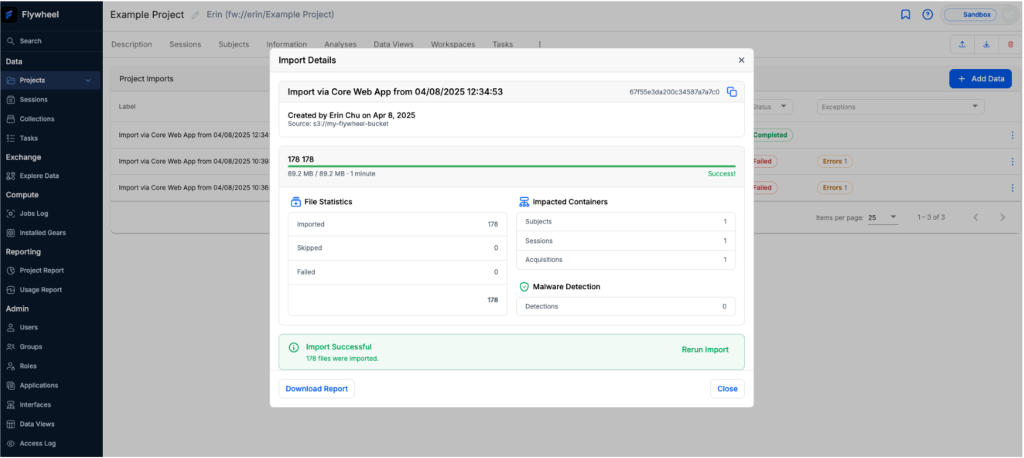

Once you have mounted your S3 bucket, you can import data into a Flywheel Project through the Web Import tool as shown in Figure 3. For this example, we’ve loaded one subject from the NSCLC-Radiomics-Interobserver1 project. This project is included in the Imaging Data Commons and is freely accessible from the Registry of Open Data on AWS.

Figure 3 – Import data into S3 Storage

Once your data has been imported into Flywheel, you can process and analyze with Flywheel Gears, leveraging configurable Amazon Elastic Compute Cloud (Amazon EC2) instances to optimize customer time and cost savings. If your Project has a Flywheel Gear Rule enabled, you can also automatically kick off data pre-processing. Our Example Project has a simple Gear Rule set up for two main purposes. First, it extracts Digital Imaging and Communications in Medicine (DICOM) header metadata. Second, it functionally classifies incoming DICOM files. The results of these processes are reflected in the Session dashboard that you see in Figure 3.